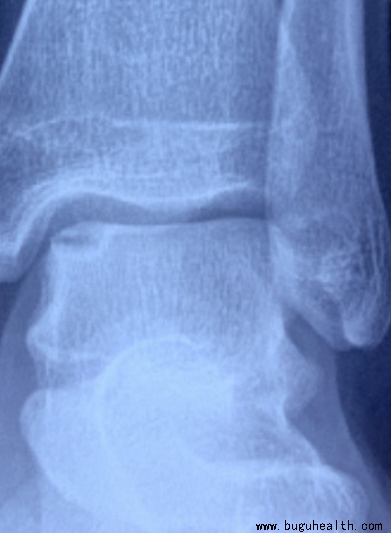

布骨医学科普:了解跟腱修复术!

跟腱是小腿三头肌,即我们小腿后侧的肌肉肌腹下端移行的腱性结构,止于跟骨结节,是人体最粗最大的肌腱之一,对我们人体行走、站立和维持平衡有着重要的意义。.....